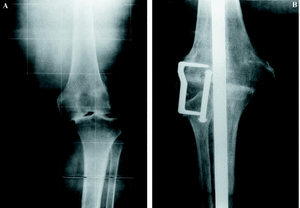

En nueve pacientes, el fracaso de la artroplastia se debió a la infección profunda (Fig. 2), aislando gérmenes del género Staphylococcus en siete de ellos. De los nueve pacientes restantes, en ocho el fracaso de la artroplastia fue debido a un aflojamiento aséptico (Fig. 3) y el caso restante fue causado por una artrofibrosis.

Figura 2. Fracaso séptico artroplastia de rodilla en mujer de 75 años. A: Radiografía preoperatoria. B: Control postoperatorio artrodesis de rodilla con clavo intramedular.

Figura 3. Fracaso aséptico artroplastia de rodilla. A: Radiografía preoperatoria, inestabilidad grave en descarga. B: Artrodesis.